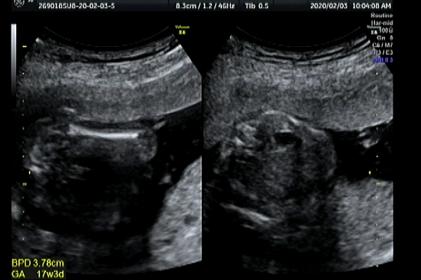

17weeks 5days ultrasound, please guess

I am new here and I am Japanese. In Japan, the doctor usually doesn't tell the gender before 22 weeks. But I already have 3 boys and 1 girl and they really would love to have one more girl so I am so nervous and would like to know the gender as soon as possible. at the 12 weeks and 0day, I thought I saw a boish nub, so I have been in a depression since. I am not sad because of the gender result but I am too afraid of what the other people will say to me if it's a boy. but when I saw the ultrasound at 17 weeks and 5 days, I saw a lips or a leave instead of penis. Is it a girl? I would like you ladies to guess the gender, please. Thanks.

Attachment 42374Attachment 42375